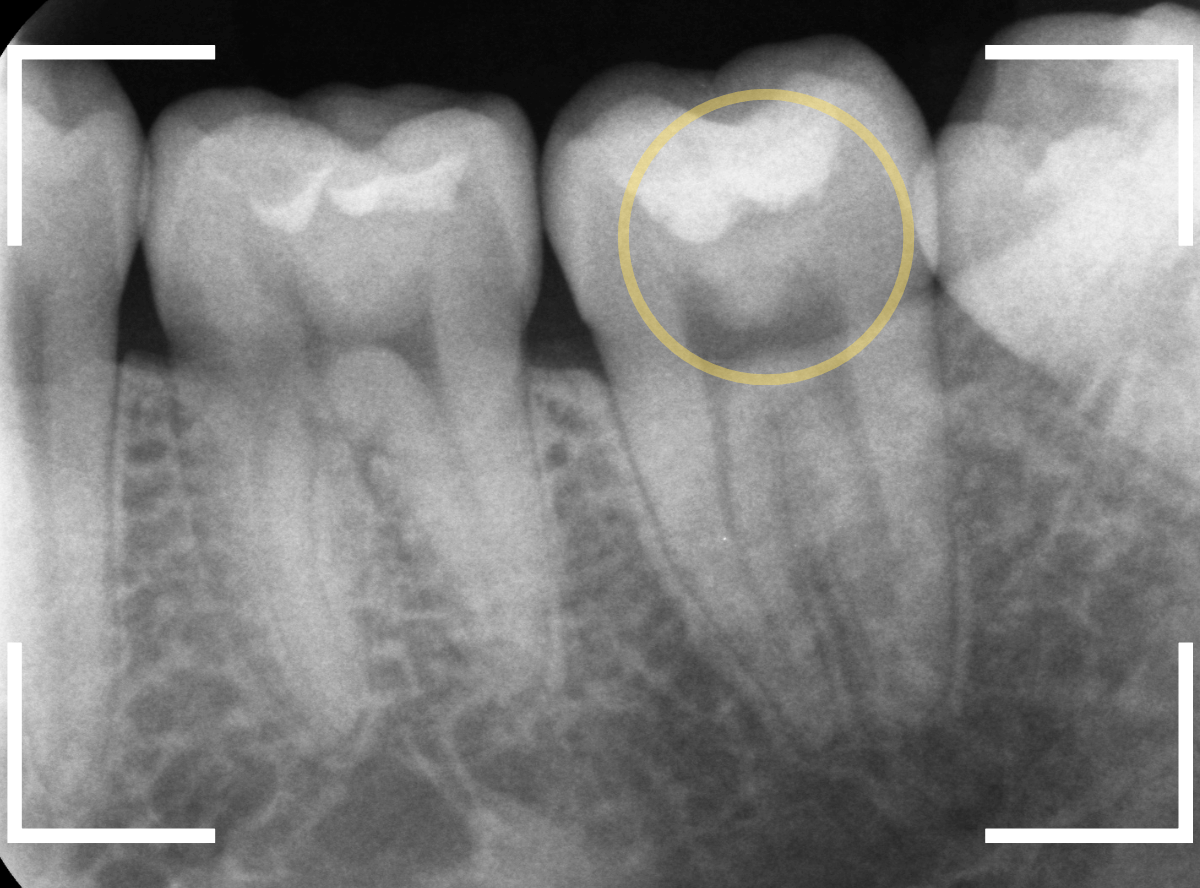

黄色い丸の部分、レジンが明らかに劣化して中が黒く透けて虫歯になっていそうです。

レントゲン写真で確認します。

レントゲンでは、黄色い丸の部分は虫歯ではなさそうに見えます。

逆に反対側のオレンジ色の丸の部分にレジンがつまっていて、中で虫歯になっていそうなのはわかります。